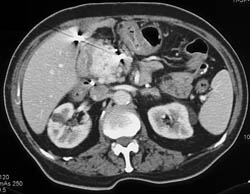

Carcinoma of the Body and Tail of the Pancreas